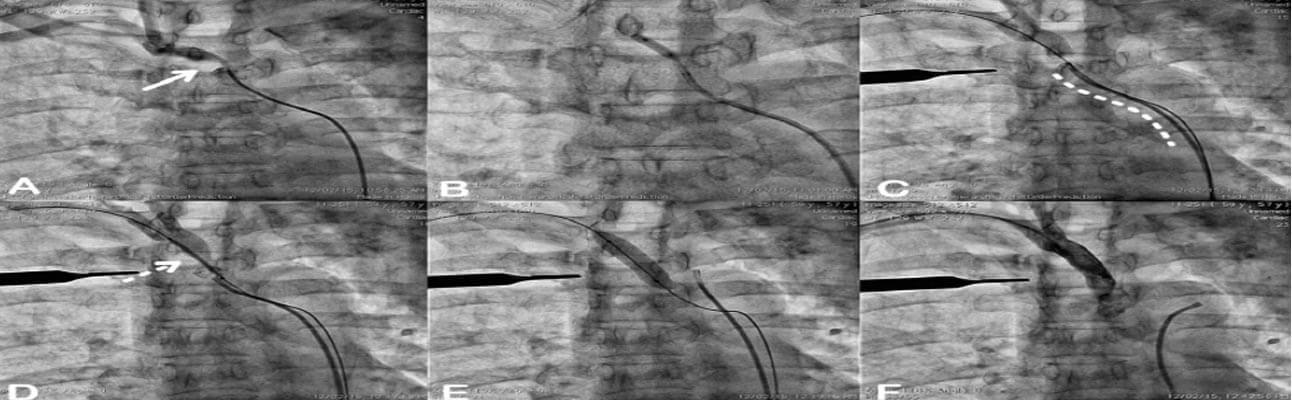

The right femoral artery was cannulated using 6Fr. sheath and 6 Fr. right coronary guide catheter to engage the right innominate artery. There was difficulty in crossing the stenosis, as it was eccentric lesion [Figure 1A]. After some efforts, whisper extra support guide wire could cross the lesion and be pre-dilated using 5.0 x 15 mm balloon [Figure 1B]. We tried exchanging with 8 Fr. Sheath but it could not be negotiated up to right brachiocephalic artery.

Hence right brachial artery was cannulated and 0.035 wire was crossed easily retrograde into the descending aorta [Figure 1C]. Through the trans-femoral approach, the right coronary diagnostic catheter was used for the visualization of the stent across the lesion [Figure 1D]. Also, the radioopaque marker [scalpel handle] was placed externally across the midpoint of the lesion and cath lab table was fixed. The 10 X 37 mm Scuba balloon-expandable stent was deployed across the ostio-proximal segment of right innominate artery [Figure 1E].

Check angiography revealed the good expansion of the stent and normal flow across the carotid-vertebral and subclavian artery [Figure 1F]. The patient had no neurological deficit and discharged on 2nd-day post procedure with the advice of optimal medical management in the form of dual anti-platelet agents [aspirin and clopidogrel], ACE inhibitor, beta-blocker, a high-intensity statin.

Step wise demonstration of peripheral percutaneous angioplasty of right brachio-cephalic artery stenosis which was eccentric [Solid arrow, Panel A] and unfavorable supraaortic takeoff [Dotted curvilinear line, Panel C] from the aortic arch. Initially, the transfemoral approach was used and could cross with coronary 0.014’ whisper extra support guide wire using a 6Fr right coronary guide catheter [Panel B]. The lesion was dilated using 5.0 x 15 mm balloon [Panel B]. For the deployment of a stent, we could not negotiate a larger 8 fr. Guide catheter/delivery sheath [Not Shown]. The transbrachial approach used to deploy 10 x 37 mm balloonexpandable stent across the lesion [Dashed arrow, Panel D] under angiographic guidance from trans-femoral right coronary diagnostic catheter [Panel E] and externally placed scalpel handle across the lesion as a radiopaque marker [Panel C-F]. Final check angiography showed no residual stenosis with the brisk flow [Panel F].